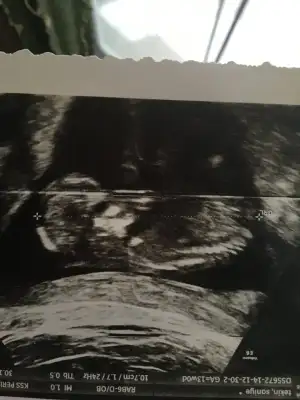

dr soylemeden siz gorun genital nub teorisi ( bebegin cinsiyeti)

Merhaba 10+1 haftalık ama ultrasonda 10+6 cıktı var mı tahminler